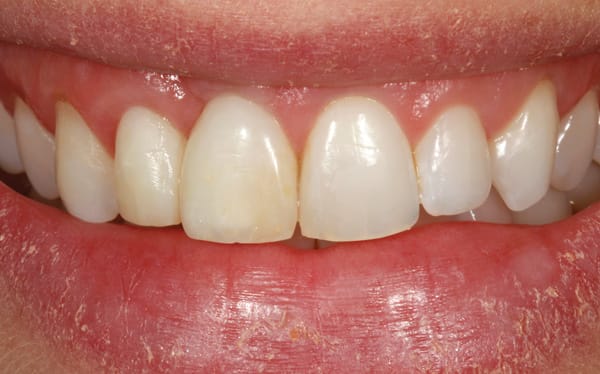

After 6 months of healing of the implant, stage 2 uncovering was performed and the mucosal tissues were allowed to mature for another 2 to 3 weeks. A temporary screw-retained implant cylinder (PreFormance® Temporary Cylinder, Biomet 3i) was joined to the implant and acrylic (Super-T, American Consolidated Mfg, www.pattersondental.com) crown (Figure 8). The subgingival shape of the temporary was modified with additional acrylic and the technique of non-surgical tissue sculpting, which was developed to provide the proper emergence profile to the mucosal tissues.27 It is important that the temporary blanching (ischemia) of the mucosal tissues dissipate after 10 minutes (Figure 9). After 3 weeks, soft-tissue scalloping through gingivectomy was done to recreate the proper shape (ie, gingival zenith)28 and proportion for the mucosal tissues (Figure 10). Fiberotomy on the distal aspect of tooth No. 7 was not performed during treatment; therefore, this papilla was slightly more incisal (longer) than the adjacent papillae (Figure 11). A final impression was made of crown No. 7 and implant No. 8 at the implant level to enable a working cast to be made in the laboratory. An all-ceramic custom abutment was made for implant No. 8 (BellaTek® Encode, Biomet 3i), and splinted full-coverage units were made for crowns No. 7 and No. 829 (Figure 12). The custom abutment was seated intraorally and torqued according to the manufacturer’s recommendation. The crowns were luted with provisional cement (Tempbond® NE, Kerr Dental, www.kerrdental.com) and maintained at 4-month recall intervals (Figure 13). Note the health of the periodontal tissues and their integration with the adjacent teeth and surrounding gingiva, taking a complex esthetic and functional problem for a patient with a high smile line and providing a predictable restorative and esthetic outcome (Figure 14).